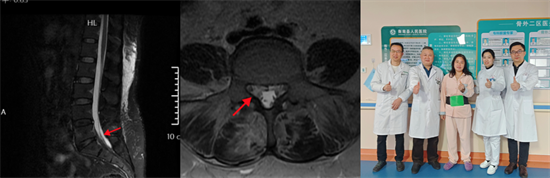

術(shù)前影像資料顯示L5/S1巨大脫出椎間盤(pán)并向近端高度游離

患者陽(yáng)某某,女,50歲,因反復(fù)腰部疼痛7年加重,并右下肢疼痛麻木半月到衡南縣人民醫(yī)院就診。骨科二區(qū)主任陳軾接診了患者,門診MRI檢查發(fā)現(xiàn)陽(yáng)女士為典型L5/S1巨大椎間盤(pán)脫出并壓迫神經(jīng)根,保守治療無(wú)效,建議手術(shù)治療。苗驚雷教授與縣醫(yī)院骨科二區(qū)專家團(tuán)隊(duì)為陽(yáng)女士量身定制了無(wú)需內(nèi)固定、創(chuàng)傷更小的UBE微創(chuàng)手術(shù)方案。術(shù)中通過(guò)兩個(gè)7mm的切口,精準(zhǔn)摘除脫出髓核,徹底解除神經(jīng)壓迫。術(shù)后次日,陽(yáng)女士下肢癥狀顯著緩解,已可自主下床活動(dòng)。